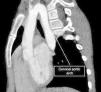

We present the case of a girl aged 9 years with DiGeorge syndrome referred to our hospital due to suspicion of right aortic arch. In the physical examination, the patient exhibited mild dyspnea, cough and occasional choking, with a palpable cervical pulse. The computed tomography (CT) scan of the heart revealed a complex vascular anomaly: a right-sided aortic arch extending cranially to the level of the right thoracic inlet, forming a cervical aortic arch (CAA) (Figs. 1 and 2, Appendix B video 1). The first branch of the aorta was the left common carotid artery, followed by the right subclavian artery, the left common carotid and the left subclavian artery (LSA). The LSA arose from a Kommerell diverticulum (Fig. 3, Appendix B video 2), which, combined with the ligamentum arteriosum, formed a complete vascular right that compressed the trachea (Fig. 3). Cervical aortic arch is an infrequent anomaly in the development of the aorta, occurring in fewer than 1 in 10 000 live births, characterized by an elongated aortic arch extending at or above the medial ends of the clavicles.1 This condition is associated with aneurysms (occurring in up to 20% of cases), coarctation of the aorta, congenital heart defects, Turner syndrome and DiGeorge syndrome.1,2 Given the presence of a complete vascular ring, surgery was the chosen treatment.3